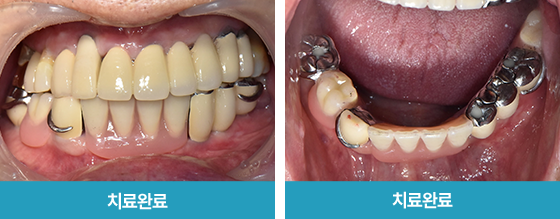

· 네비게이션 임플란트 / 상하악 식립 case

치료 후 사진

3~4개월 전 타치과에서 시술 마무리하였지만

불편한 곳이 또생겨 검진 진행한 케이스

하악 발치 진행 후 임시틀니 사용,

이후 임플란트 식립 2달 뒤 체결하며 최종 부분 틀니 완성

*환자분 비용부담 보험임플란트 2개,

보험틀니 활용하여 적은 비용으로 하악치료 완성